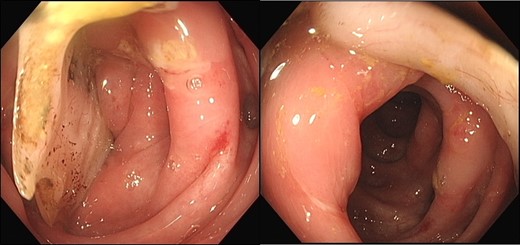

A 52-year male was referred to the surgical team for a 1-day history of left iliac fossa pain accompanied by nausea and the inability to open his bowels for 48 hours. The pain was 9/10 in severity, sharp, persistent and with a gradual worsening onset. The patient was previously diagnosed with extensive diverticular disease and admitted 2 months prior with acute sigmoid diverticulitis. 18 months earlier he underwent an emergent laparoscopy for an unclear pelvic inflammatory mass on CT, that suggested either severe sigmoid diverticulitis or appendicitis. He also had multiple polyps throughout the colon, that were endoscopically removed. The patients past medical history was significant for a non-flow limiting coronary artery disease, arterial hypertension and an allergy to penicillin and tetracycline. Temperature on admission was 38.7 C, blood pressure of 149/109 mm/Hg, pulse of 109 bpm and a respiratory rate of 20/min with O2-saturations of 96% on room air. The abdomen was soft with tenderness and guarding over the left iliac fossa. Bowel sounds were present. Investigations showed a white cell count of 17.6 tsd/ul and a CRP of 64 mg/l. No pneumoperitoneum was detected on an erect chest x-ray. Treatment with ciprofloxacin and metronidazole was started and the patient kept nil per mouth. CT imaging showed extensive sigmoid diverticular disease with marked pericolonic fat stranding and free gas tracking into the mesenteric fat. Gentamycin was added and within 3 days the patient’s clinical symptoms improved. He was apyrexic and the white cell count dropped to 10.9 tsd/ul. A repeat CT scan showed a stable appearing localized perforation with reduced free gas and no signs of collection. However, of note was a small curvilinear metallic foreign body within the lumen of the sigmoid colon of uncertain etiology (Fig. 1). On questioning, the patient recalled a mechanical fall with a head contusion 9 days prior to admission during which he lost his partial denture. The patient was commenced on laxatives and despite bowel movement on the following day, the foreign body did not pass. A PFA showed the persistent presence of the metallic foreign body over the sigmoid colon, which raised the suspicion of impaction (Fig. 2). The patient was prepared for colonoscopy and the foreign body was identified impacting the lumen of the sigmoid colon (Fig. 3). However, endoscopic retrieval failed and the decision was made to proceed with laparoscopic anterior resection. Intraoperative findings showed a rigid and thickened sigmoid colon with adhesions and a diverticular abscess. About 22 cm of sigmoid colon was resected and the procedure was completed with a primary colo-rectal end to end anastomosis, using a 31 mm CEEA-Stapler. The resected sigmoid colon contained the lost partial denture, which showed impaction and perforation into the sigmoid mesocolon (Fig. 4). Following surgery, the patient was transferred to the surgical ICU for 24 h observation and discharged home after one week.

Colonoscopy identified a non-retrievable foreign body impacting the lumen of the sigmoid colon.